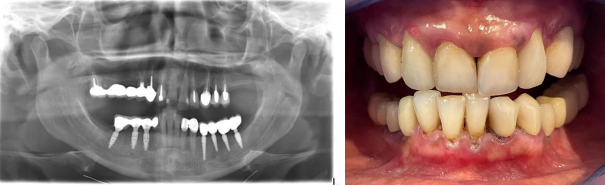

After consultation, plan was made as follows: to extract remaining teeth in the maxilla and mandible, the existing crowns on implants in the mandible were to be changed to have the same color for all the teeth (Vita B1) in the mouth Fig 1.

Figure 1 shows the panoramic radiograph and clinical photo at presentation.

Figure 1